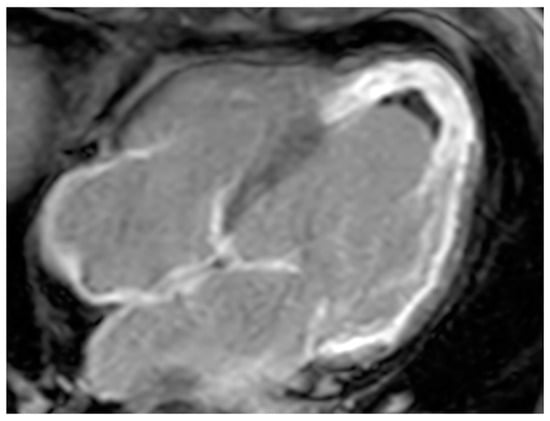

| Thrombus | Adulthood | LA, LAA (AF) LV (MI) | Asymptomatic, embolic events | Non-enhancing Intracardiac lesion | Acute: Low echodensity, rounded with smooth contours Chronic: High echodensity, linear or crescentic lesions along the endocardial surface | Low attenuation, no contrast enhancement, chronic thrombus may be calcified Usefulness of delayed CT imaging, as in the LAA stasis of blood can simulate a thrombus on early arterial images | Acute: hyper T1w and T2w Subacute: hyper T1w and hypo T2w Chronic: low T1w and T2w No enhancement. |

| Myxoma | Adulthood. Carney complex. | LA | Usually, asymptomatic. Rarely, intracardiac obstruction, embolic events and constitutional symptoms | Mobile mass arising from the IAS | Globular or spherical, with a friable surface and heterogeneous internal echogenicity | Heterogeneous, low attenuation, may be calcified | Isointense T1w, High T2w, heterogeneous LGE |